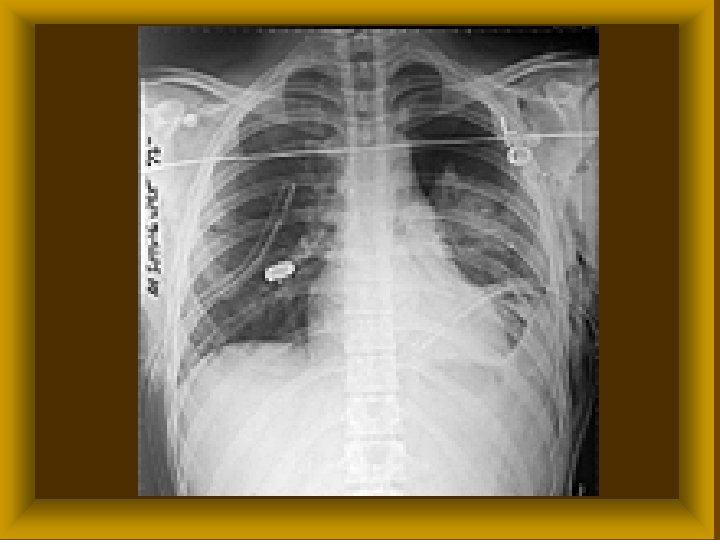

ELSŐDLEGESEN ZÁRJUK A SEBET MINDEN ESETBEN ØMellüreget ØHasfalat ØKemény agyburkot áthatoló sérülésekor

HÁBORÚS SÉRÜLÉSEK ELLÁTÁSA A háborús sérülést aerob és anaerob baktériumokkal fertőzöttnek kell tekinteni Ø A sérültek reactiokészsége elmarad a normálistól Ø Az ellátás körülményei háborúsak ezért Ø elsődleges ellátást nem végzünk, kivétel koponya, mellkas, has áthatoló sérülése Ø